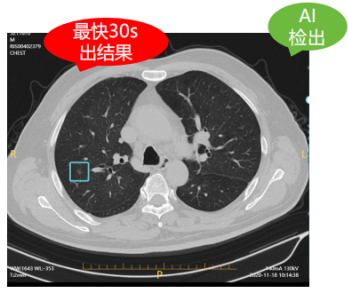

以肺結(jié)節(jié)人工智能篩查為例,正常的一個肺部CT平掃檢查具有幾百張片層,而一位熟練的診斷醫(yī)生想要從這些復(fù)雜的影像中發(fā)現(xiàn)并診斷病灶可能需要花上20-30分鐘,甚至是更長時間。而通過AI智能影像輔助診斷技術(shù)的精準(zhǔn)定位與檢測,自動檢出實性、磨玻璃、鈣化以及混合結(jié)節(jié)、疑似腫塊等,僅需30秒便可自動生成結(jié)構(gòu)化影像報告供醫(yī)生審查,雙肺結(jié)節(jié)檢出率高達99.64%!對0.5mm的微小結(jié)節(jié)都能瞬間定位,快速標(biāo)記結(jié)節(jié)大小、密度,并初步分辨良惡性,有效幫助醫(yī)生更加精準(zhǔn)篩查肺結(jié)節(jié),使肺癌患者及早得到良好診治。